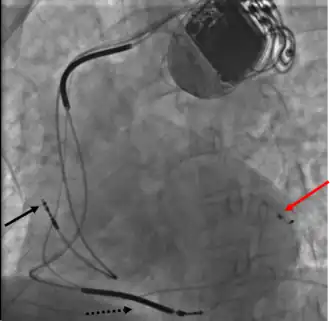

Right ventricular lead placement

A venipuncture is made, and a guide wire inserted into the vein, where it is guided, with use of real time X-ray imaging, through to the right ventricle. The guide wire is then used to assist in the placement of the electrode lead, which travels through the venous system into the right ventricle where the electrode is embedded.[1]

Left ventricular lead placement

This is generally performed subsequent to RV lead placement, with the RV lead providing a backup in case of accidental damage to the electric fibers of the heart, causing an asystolic event. As with the RV lead, a guide wire is first inserted, allowing for the insertion of a multi-delivery catheter. The catheter is subsequently maneuvered to the opening of the coronary sinus in the right atrium. From here a contrast media is injected, allowing the surgical team to obtain a coronary sinus phlebogram to direct the placement of the lead into the most suitable coronary vein.[1]

Once the phlebogram has been obtained, the multi-delivery catheter is used to guide in the lead, from the chosen vein of entry, into the right atrium, through the coronary sinus and into the relevant cardiac vein.[1]

Left ventricular lead placement is the most complicated and potentially hazardous element of the operation, due to the significant variability of coronary venous structure. Alterations in heart structure, fatty deposits, valves and natural variations all cause additional complications in the process of cannulation.[1] However, this risk can be reduced using AI-based[8] preoperative visualization of LV venous anatomy using computer tomography (CT) imaging.